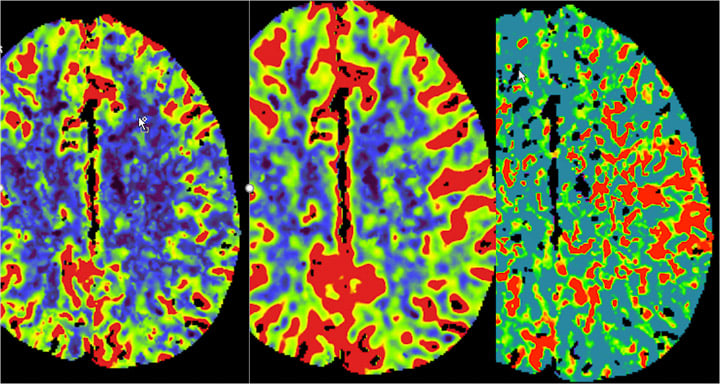

- Stroke (ischemic and hemorrhagic)

- 8 clinical MR systems

- 1 research 3T MR system